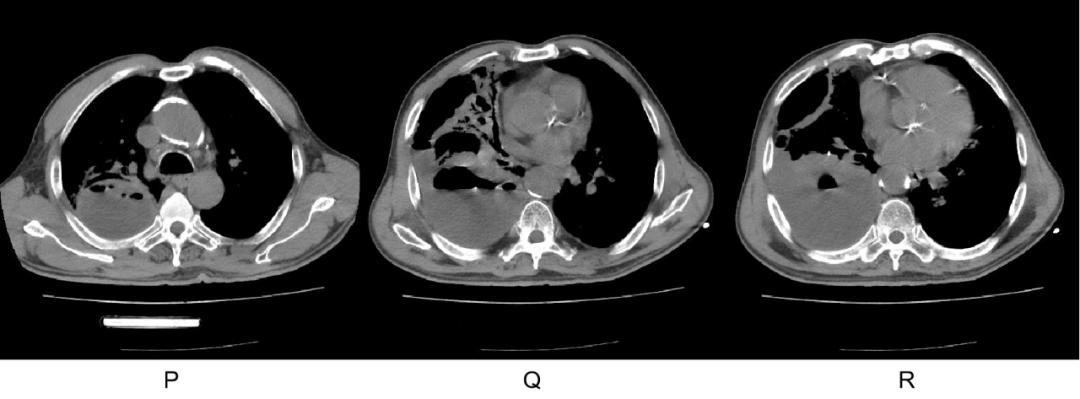

2022-1-2 入院时

2022-1-4 进展时复查 CT

2022-1-14 治疗后

原高张力肺脓肿及脓胸间隔 2 天病灶迅速进展,出现液气平面,大剂量青霉素+奥硝唑治疗 8 天明显好转。